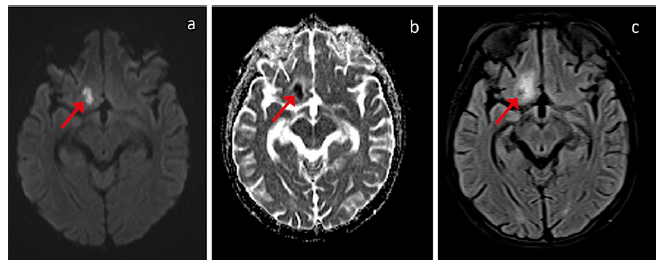

Posteriormente, la angiorresonancia cerebral contrastada evidenció una alteración en el calibre y la morfología de los vasos arteriales en la circulación anterior distal, sugestivo de vasculitis. Además, se observó un pequeño foco de restricción a la difusión por lesión de tipo isquémico en la región frontal derecha, con hiperintensidad en T1, que sugiere la presencia de conversión hemorrágica (figura 1). Ante estos resultados y por la persistencia de los síntomas neurológicos, se adicionó ciclofosfamida según el protocolo del National Institute of Health (NIH), acetazolamida y ácido acetilsalicílico, con posterior mejoría del estado general y neurológico.

Angiorresonancia cerebral. 1a y 1b) Imágenes de resonancia cerebral en secuencias de difusión, donde se identifica la lesión frontal basal derecha que restringe la difusión. 1c) Imagen de resonancia cerebral ensecuencia FLAIR, donde se identifica la lesión hiperintensa frontal derecha

Figura 1: Angiorresonancia cerebral. 1a y 1b) Imágenes de resonancia cerebral en secuencias de difusión, donde se identifica la lesión frontal basal derecha que restringe la difusión. 1c) Imagen de resonancia cerebral ensecuencia FLAIR, donde se identifica la lesión hiperintensa frontal derecha